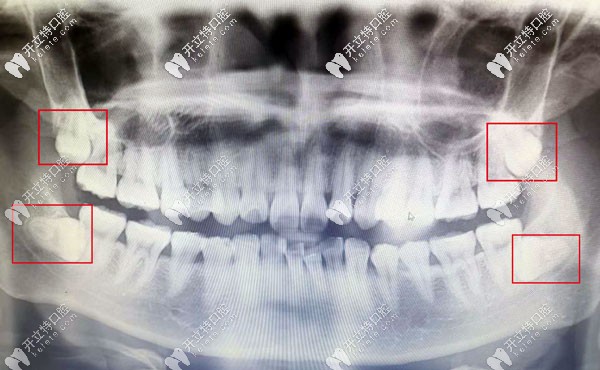

口腔的智齒反復(fù)發(fā)炎導(dǎo)致臉頰膿穿案例:

王女士已經(jīng)45歲,因左下智齒反復(fù)發(fā)炎未完全治療,導(dǎo)致智齒冠周炎伴向瘺,面部腫大,膿腫已經(jīng)把左側(cè)臉頰擊穿。

考慮到顧客患病時間久,導(dǎo)致智齒根尖局部炎癥范圍較大,智齒牙根距離下牙槽神經(jīng)管較近,面部膿腫組織需要切除,切除后的縫合難度也是比較大的。首先需要消除炎癥。